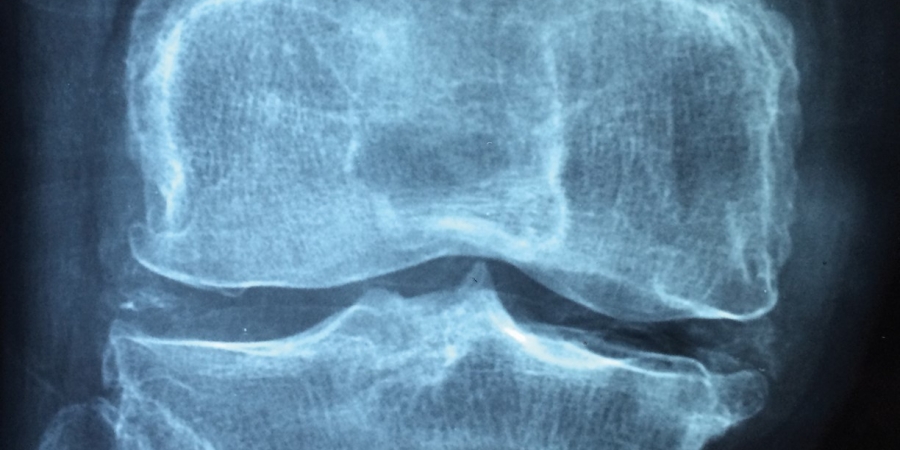

Krankheitsbild Arthrose

Schmerzende Gelenke plagen die Betroffenen mit Schmerz, Schwellungsneigung, reduzierter Funktionsfähigkeit, Bewegungseinschränkungen und einschneidendem Verlust an Lebensqualität. Oft kommt dann die ärztliche Diagnose: „Sie haben Arthrose.“ Aber was bedeutet das eigentlich?

Mittlerweile werden degenerative Veränderungen, wie Knorpelschäden, Bandscheibenvorwölbungen, Meniskusrisse oder Osteophyten, nur noch als Begleitdiagnosen betrachtet. Viele Studien belegen, dass vermeintlich degenerative Erscheinungen an Knorpel, Bandscheiben, Gelenken oder Sehnen so normal sind wie graue Haare oder Falten in der Haut. Sie hängen mehr mit dem Lebensalter zusammen als mit dem Bestehen einer symptomatischen Arthrose.

Zudem sind sie auch bei völlig symptomfreien Probanden zu finden. Wenn sie also nicht zwingend Schmerzen verursachen, so ist der Umkehrschluss statthaft: Bei bestehenden Schmerzen sind nicht obligatorisch die gefundenen Veränderungen die Ursache.

Was Arthrose tatsächlich ist

Bei Arthrose handelt es sich nach neueren Erkenntnissen um eine geringgradige und langfristige Entzündung der Gelenkoberfläche. Es geht weder um einen rein mechanischen Abrieb der Knorpelflächen noch um einen rein mechanischen Verschleiß der gelenkbildenden Strukturen. Vielmehr ist das Immunsystem aus dem Gleichgewicht, weil vielfältige Fehlschaltungen es in einen sogenannten proinflammatorischen, also einen Entzündung unterstützenden Zustand geraten ließen.